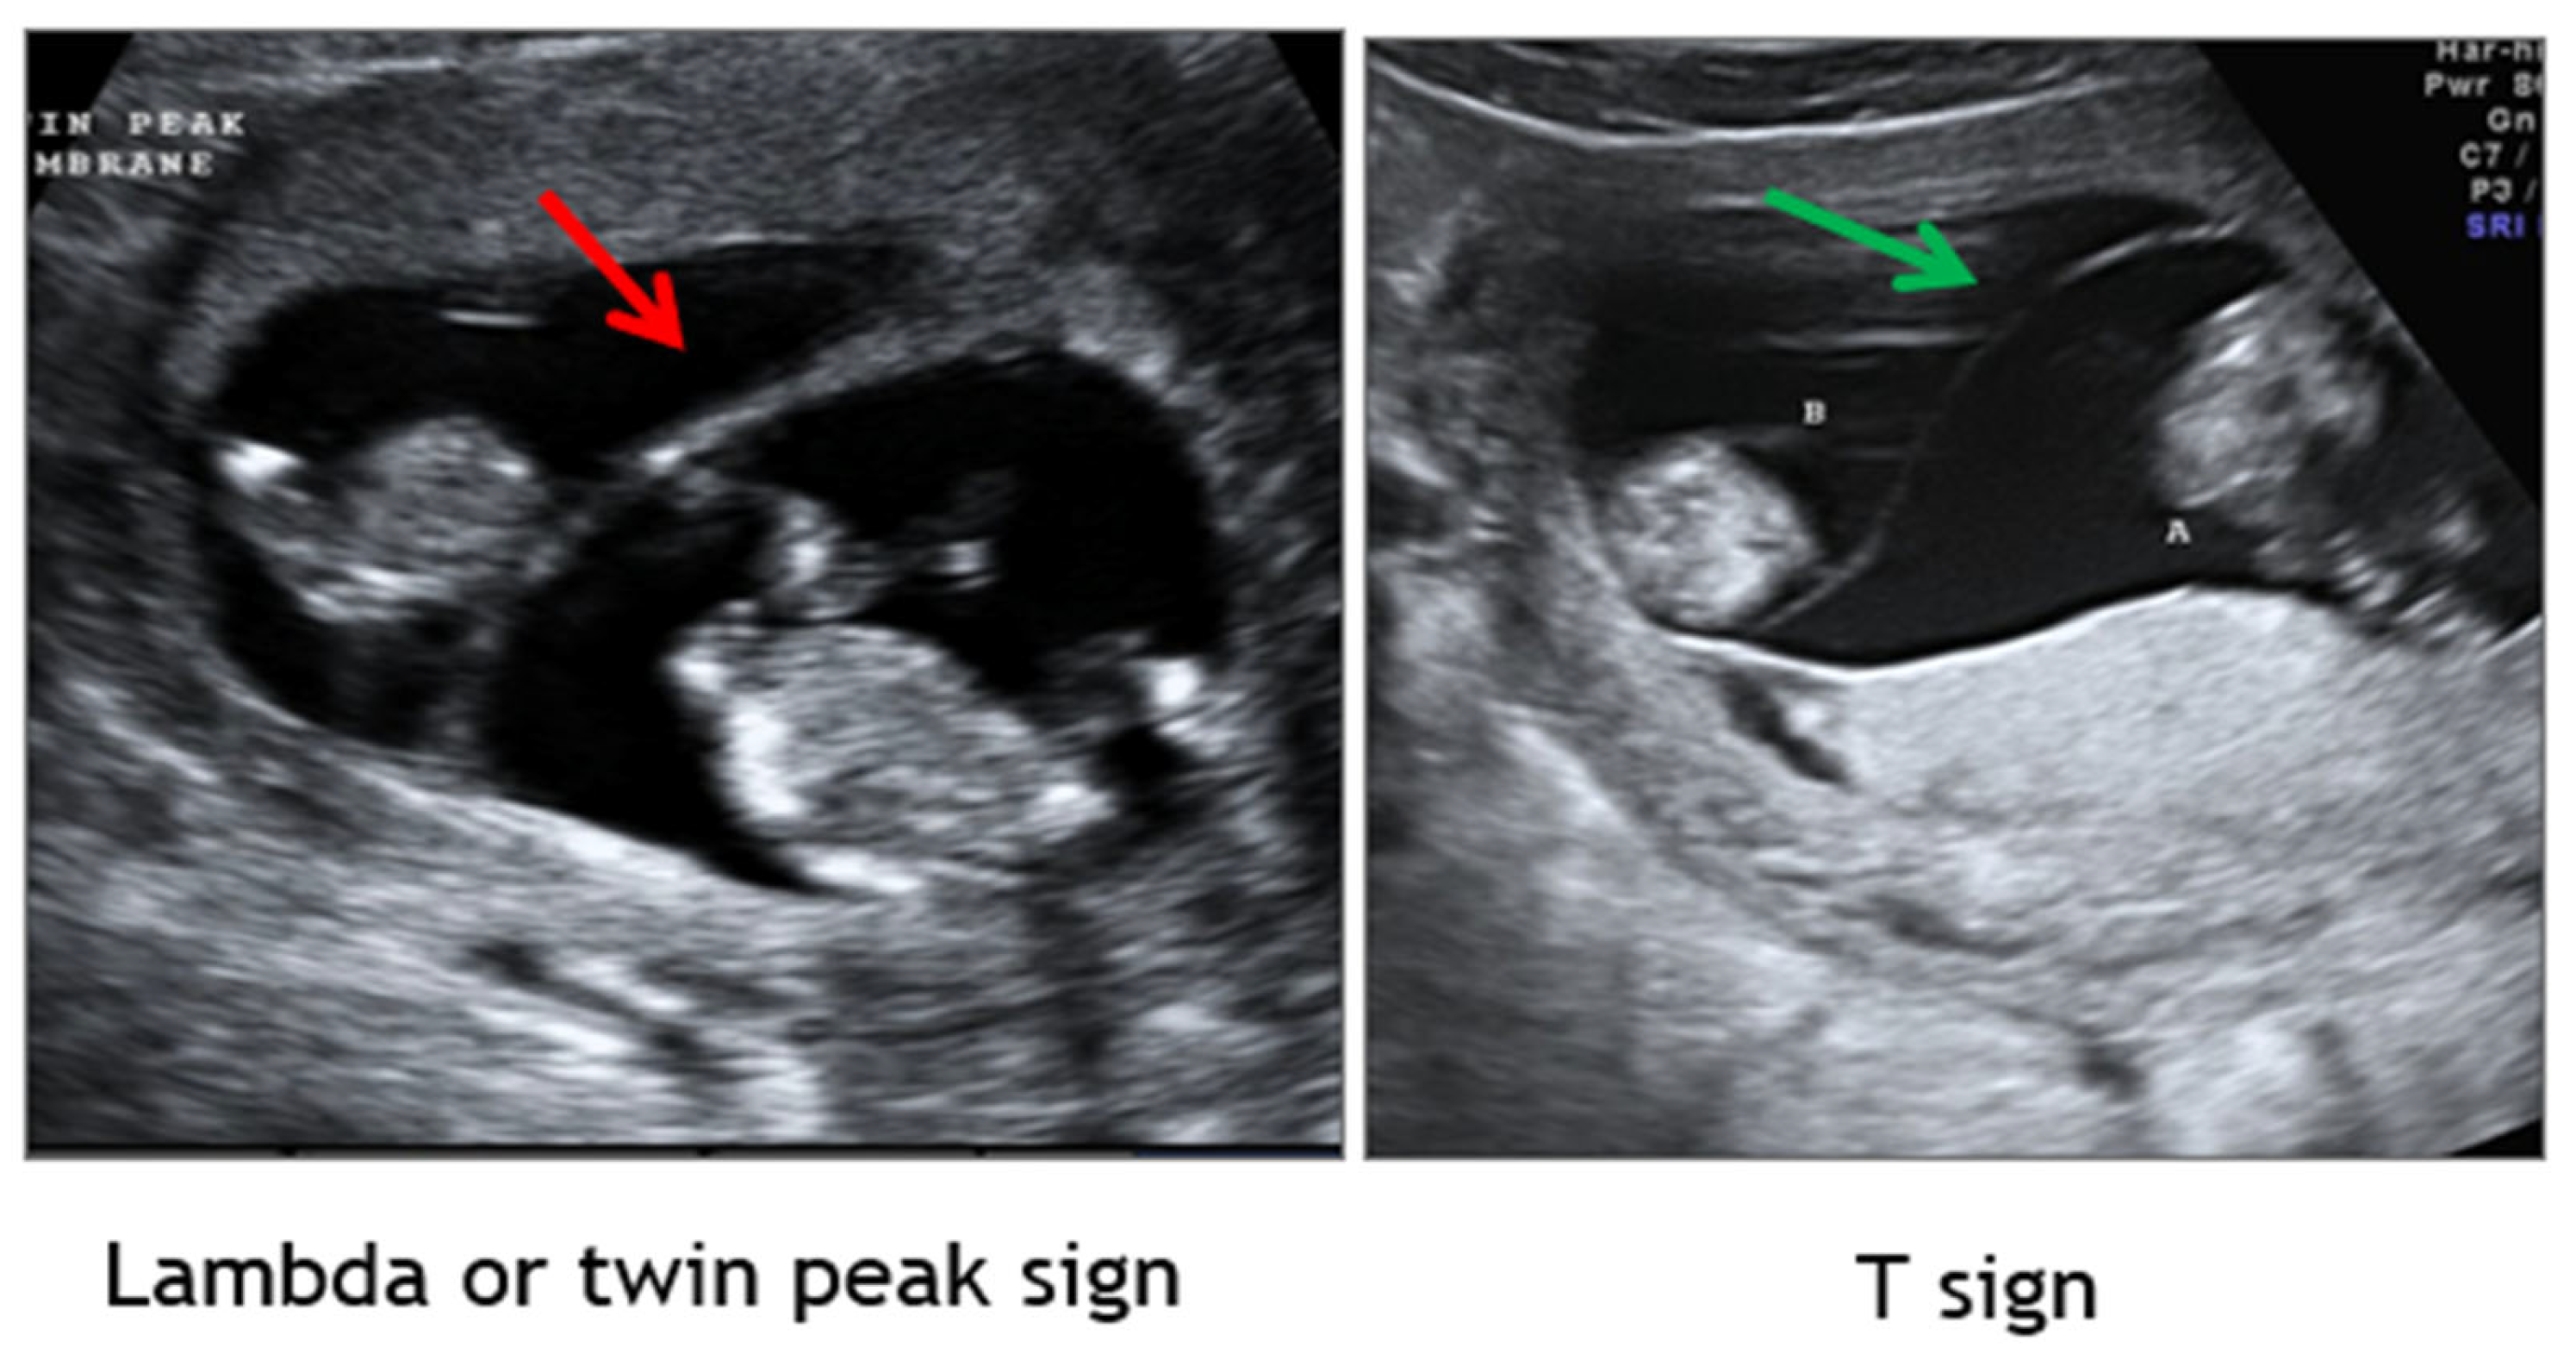

1.2. Establishment of Chorionicity and Amnionicity

- First trimester ultrasound remains paramount in discerning chorionicity in twins and high order multiple gestations [Level II-2A; B].

- Maruotti, G.M.; Saccone, G.; Morlando, M.; Martinelli, P. First-trimester ultrasound determination of chorionicity in twin gestations using the lambda sign: A systematic review and meta-analysis. Eur J Obstet Gynecol Reprod Biol. 2016, 202, 66-70. [Meta-analysis of twins, n=2292 from 9 studies; Level IIb; B]. [CrossRef]